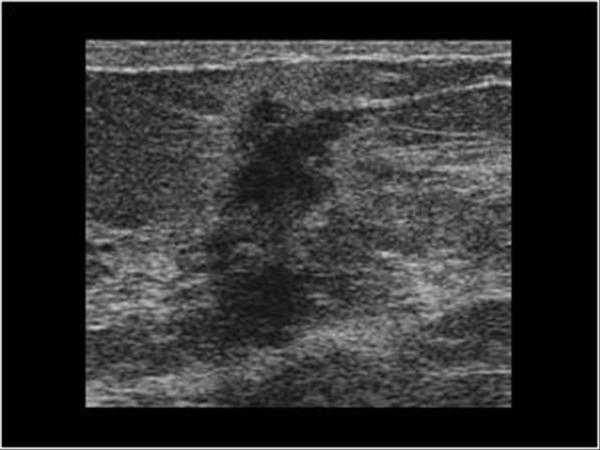

Ung thư vú

» Thông tin: Nữ giới – 59 tuổi.

» Lâm sàng: Khối tuyến vú.